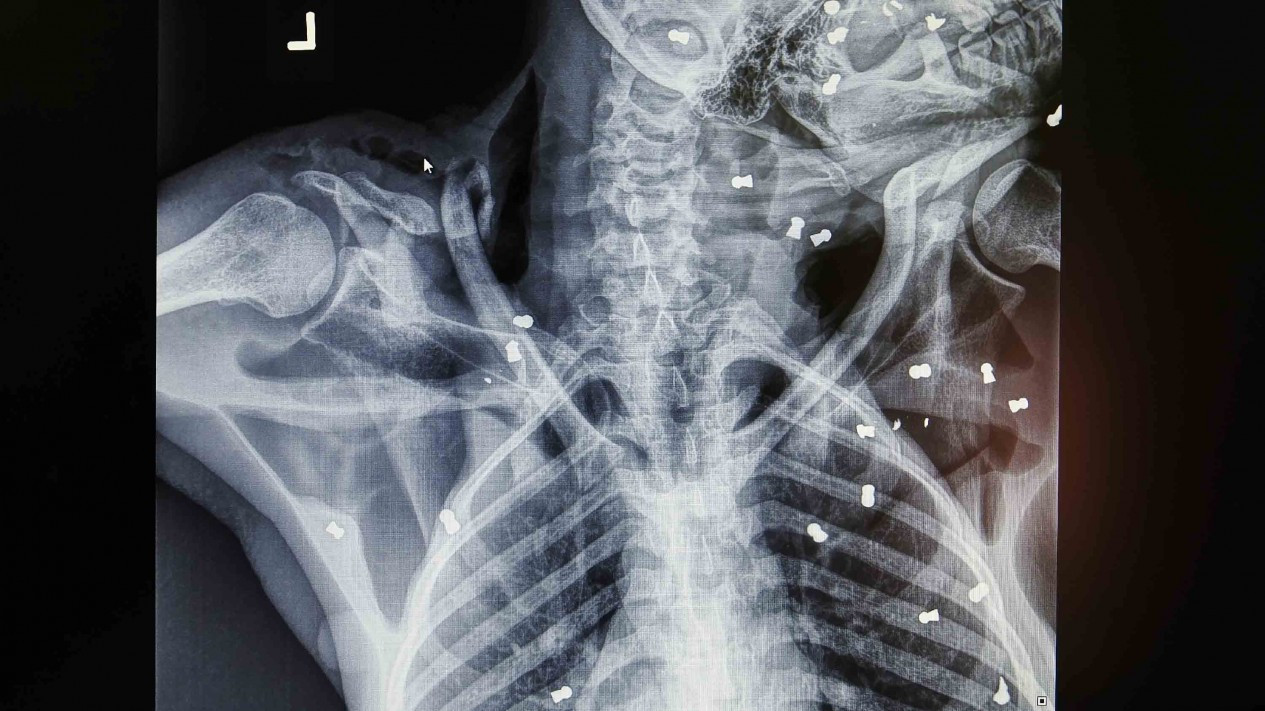

VIVA – Hasil pemeriksaan menunjukkan terdapat 74 peluru senapan angin dibadan dan wajahnya sehingga menyebabkan buta total di kedua matanya. Selain itu Orangutan Hope juga mengalami patah tulang di bahu kiri serta dengan luka-luka benda tajam di sekujur tubuh dan kemudian menjalani operasi patah tulang dengan bantuan seorang ahli bedah tulang dan syaraf dari Swiss Dr. Andreas Messikommer, seorang relawan dokter yang sudah beberapa kali membantu tim medis YEL-SOCP menangani kasus serupa.